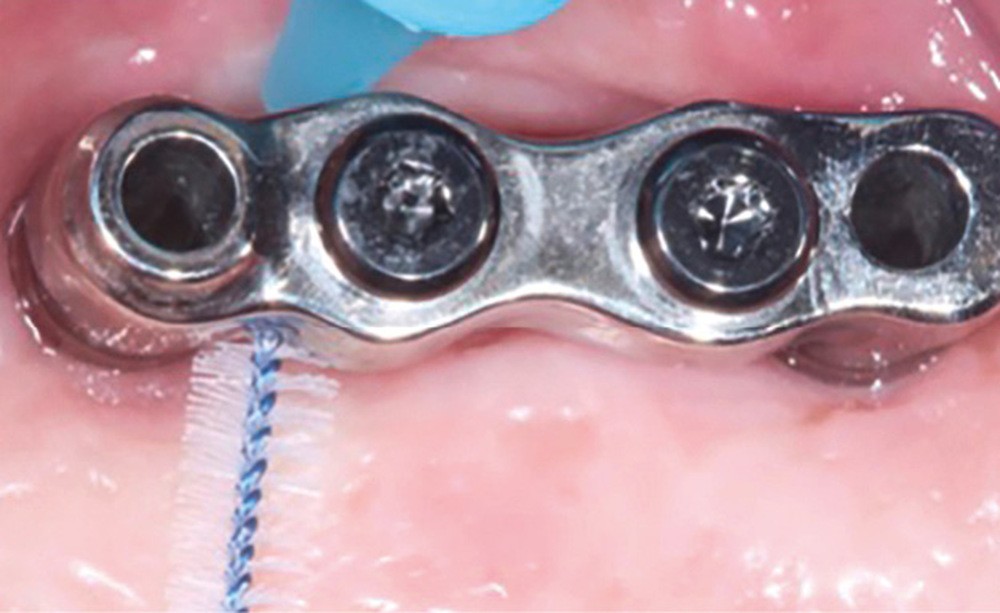

Enfin, la conception prothétique elle-même est à réfléchir, que ce soit en termes de profil d’émergence [18, 19] (pas de surcontour par exemple) (fig. 8) que d’accès à l’hygiène [20, 21] (fig. 9).